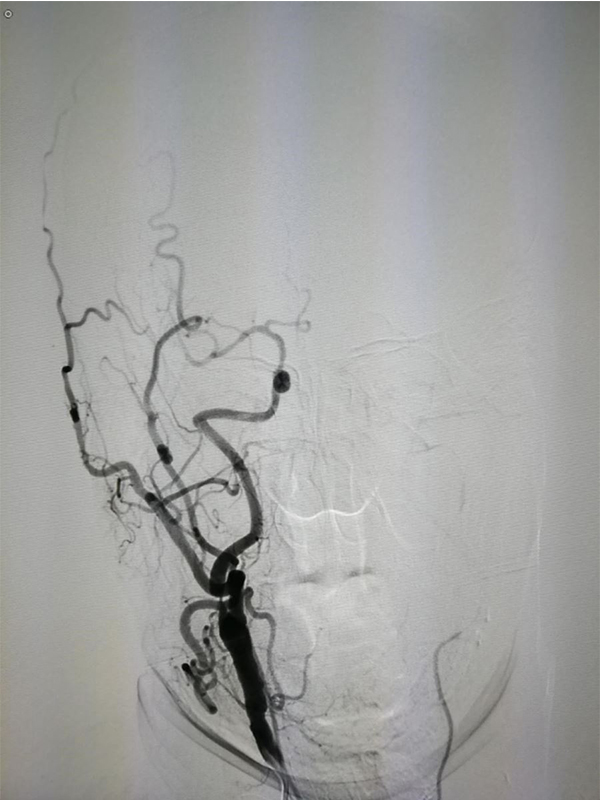

MRA CTA (CT ) DSA <50 %) MRA 50 % CTA 80% DSA 99 % ( ) CTA DSA

MRA CTA (Willis) CT

CTA 100 % 63 %(95 % 25 %-88 %) 70 % 100 %